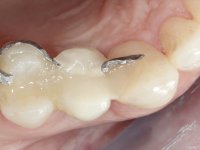

A CT scan was performed to evaluate the available bone heritage and to choose the type and size of implant to be placed. An impression of both jaws was made in alginate, as well as intermaxillary recording for laboratory work on a provisional prosthesis. The provisional prosthesis was made by including a metal wire in a prosthetic tooth adapted to the edentulous space. The root was carefully removed and the implant was placed in the tooth socket corresponding to tooth 1.4. The remaining space between the walls of the alveolus and the implant was filled with regenerative material and then sutured. The prosthesis was previously adapted to the postoperative zone and was then bonded to adjacent teeth. Teflon was used to promote the best possible insulation. Bonding was done using photopolymerizable composite resin using the palatine and inter-proximal walls of the adjacent teeth. After 10 days, the suture was removed and one month later osseointegration was confirmed. Exposure of the implant and placement of the healing screw was performed after 10 weeks. The cervical portion of the provisional tooth had to be reduced to accommodate the healing screw. Stabilized peri-implant soft tissues were impressed using open tray technique with soft and regular consistency putty silicon. In the laboratory the work model was made, along with the choice of pre-fabricated components for the confection of a metal-ceramic crown screwed to the implant with the brand’s interface. Removal of the provisional bridge was done with great care not to touch the interproximal surfaces of the teeth adjacent to the edentulous space. The crown was screwed to the implant, and after imaging, the seating was given the final tightening with 35N of torque. The screw access hole was filled with Teflon and closed with composite resin. The patient manifested satisfaction with the aesthetic and functional rehabilitation achieved.